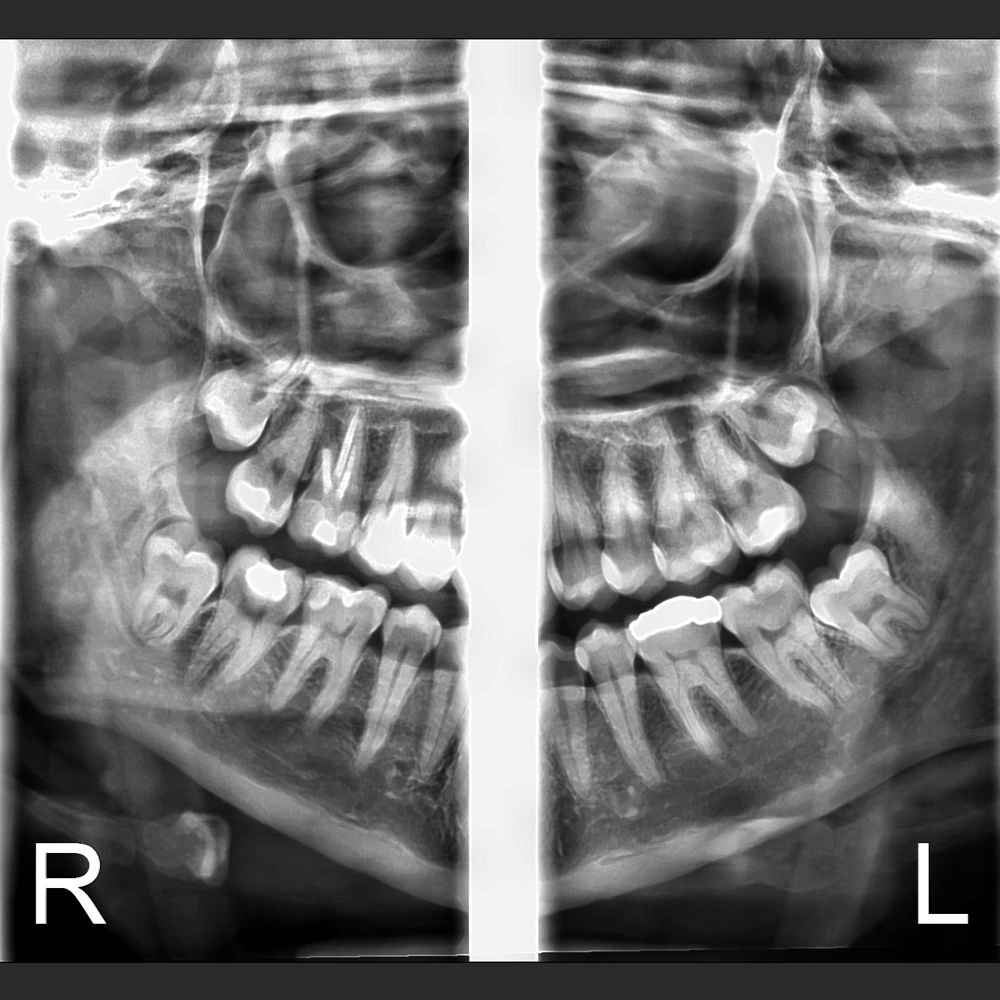

Sistema robotico de movimientos suaves y sin vibraccones, especialmente desarrollado para las imagenes de ultradefinición en endodontia. El sistema de movimientación de ultima generación Eagle presenta tres ejes, siendo dos direcciones ortogonales y una rotación permitiendo más flexibilidad en la elaboración de los perfiles radiograficos optimización de espesor de plan de corte. Ampliación vertical cnstante y como consecuencia mejores imagenes.

Eagle Smart Contrast®

El algoritmo Eagle Smart Contrast® es una herramienta innovadora que actúa en todas las regiones de la imagen, tratando y perfeccionando el contraste de cada área individualmente. El resultado es uns imagen homopgénea y sin ruido, permitiendo la visualización de detalles y consecuentemente un mejor diagnóstico.